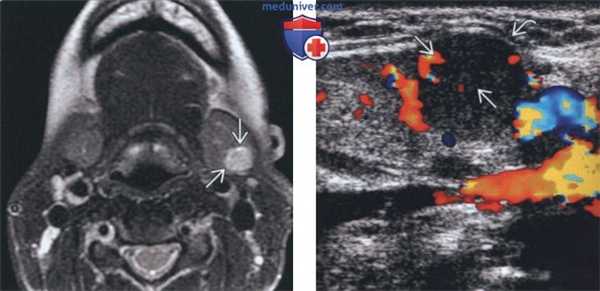

(Справа) На аксиальной КТ с КУ у другого пациента определяется неравномерное диффузное увеличение правой ПНЖ. Очаговое обызвествление с внутренней стороны позволяет заподозрить ДСО. Томография не позволяет различить злокачественную и доброкачественную опухоль за исключением случаев с явными признаками инвазии или лимфаденопатии. (Слева) На аксиальной МРТ (Т2 ВИ) у молодой женщины с пальпируемым образованием в поднижнечелюстной области в левой ПНЖ визуализируется хорошо отграниченная опухоль овальной формы с гиперинтенсивным сигналом. Признаки распространения опухоли за пределы ПНЖ отсутствуют.

(Справа) На цветовой допплеровской сонограмме у этой же пациентки в левой ПНЖ визуализируется хорошо отграниченное солидное образование, деформирующее наружный контур железы. В образовании не определяются кальцинаты или кистозные изменения, присутствует периферический и внутренний кровоток.

(Слева) На аксиальной МРТ (Т2 ВИ) у молодой женщины с пальпируемым образованием в поднижнечелюстной области в левой ПНЖ визуализируется хорошо отграниченная опухоль овальной формы с гиперинтенсивным сигналом. Признаки распространения опухоли за пределы ПНЖ отсутствуют.

(Слева) МРТ Т2ВИ, аксиальная проекция, молодая пациентка с пальпируемым образованием в поднижнечелюстной области. В левой поднижнечелюстной железе видно гиперинтенсивное образование овальной формы. Признаков распространения за пределы железы нет.

(Справа) Допплеровское УЗИ, продольная косая проекция, эта же пациентка. Солидное образование с четкими контурами в левой поднижнечелюстной железе. Контуры железы деформированы. Кальцификатов или кист в толще железы нет. На периферии и в центре опухоли кровоток сохранен.